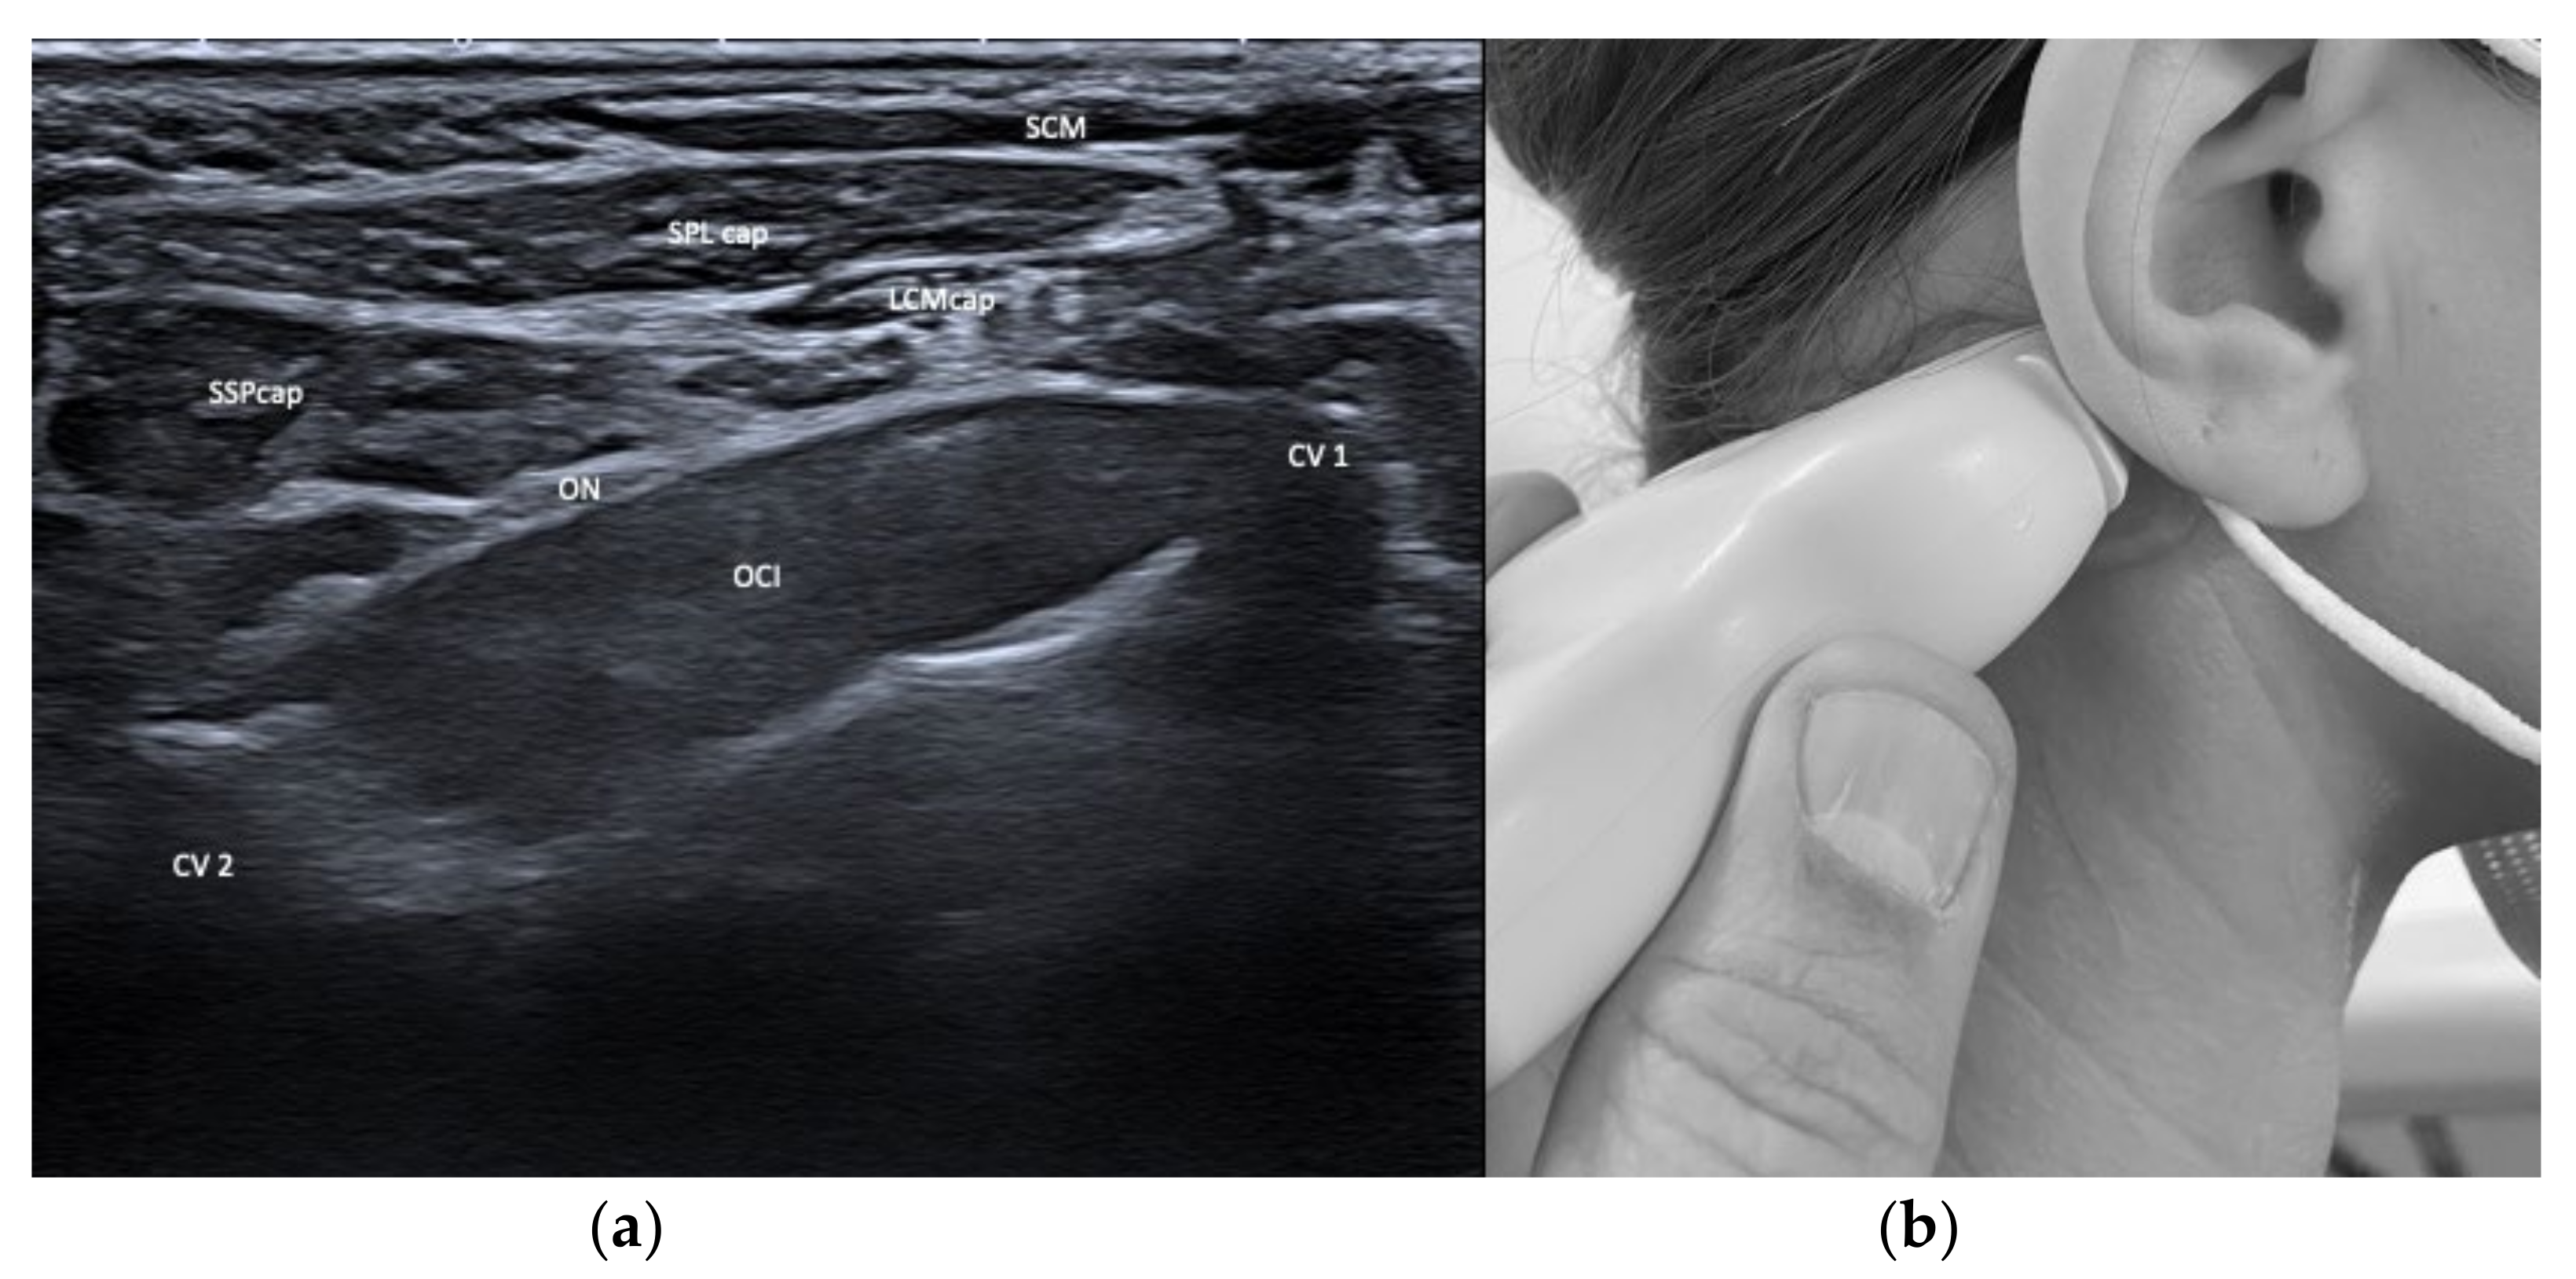

| Semispinalis capitis (SSPcap) | Extension of head | + | + | SPLcap, OCI | Strongest extensor muscle of head and neck |

| Splenius capitis (SPLcap) | Ipsiversion of head | ++ | ++ | major occipital nerve, SPLcap/cer, LSMcap, OCI | Prominent reduction in bulk from repeated injections possible |

| Longissimus capitis (LCM) | Ipsiversion of head and neck | +++ | ++ | SPLcap, SSPcap | Obligatory USG |

| Obliquus capitis inferior (OCI) | Ipsiversion of head | +++ | +++ | SSPcap, RCM, vertebral artery, greater occipital nerve | Adjacent muscles are all extensors of the head |